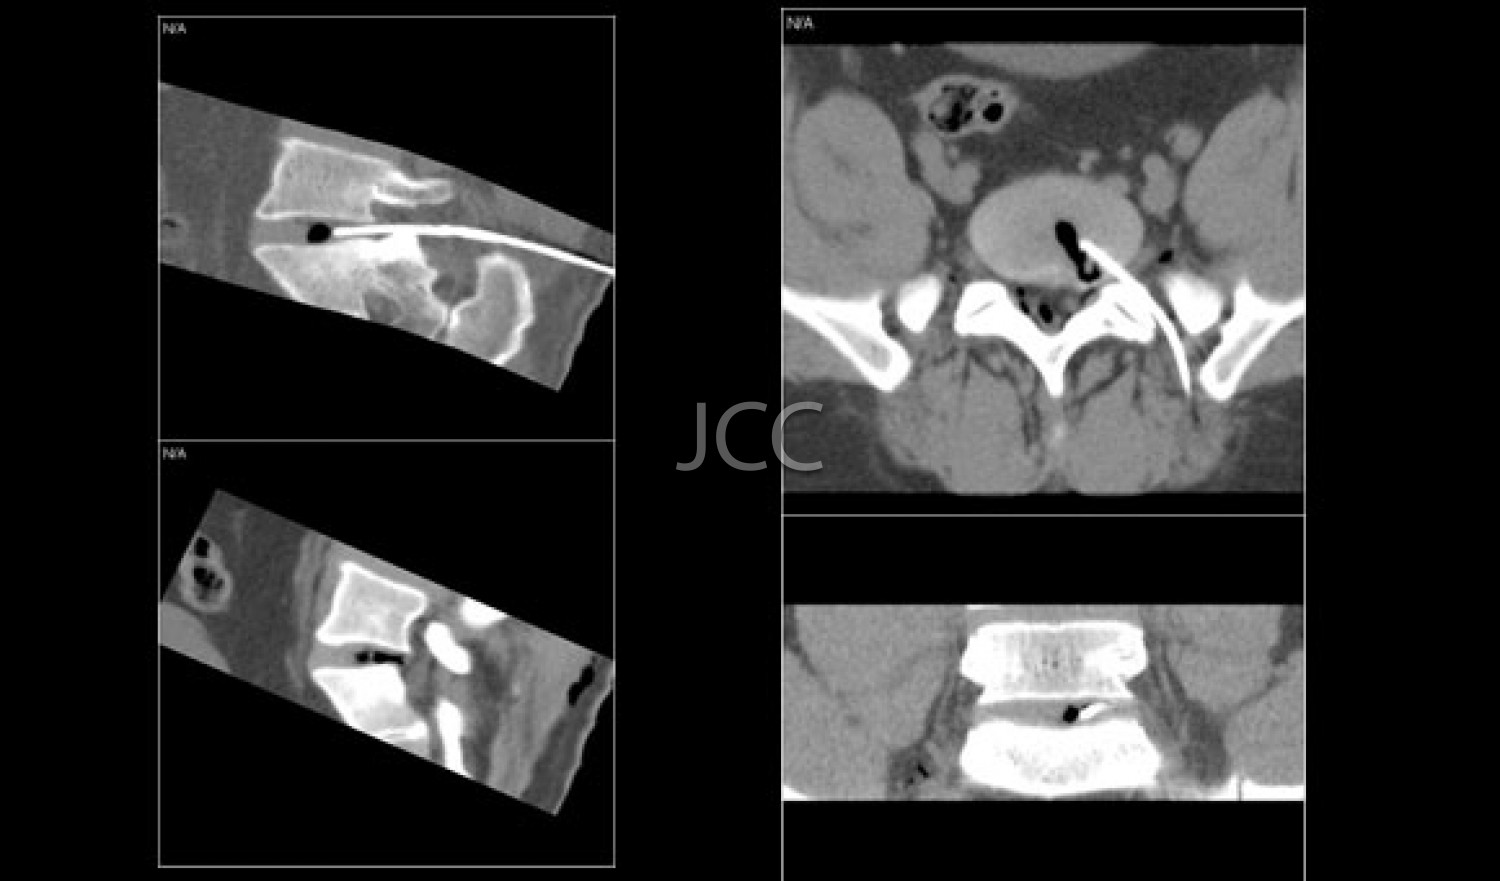

- Interventional Radiology